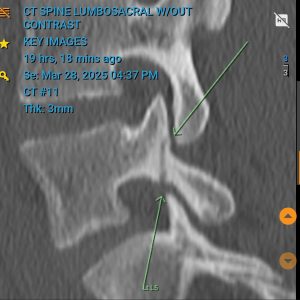

3mmFracture

The scan indicating the 3mm fracture.

Unfortunately, follow-up scans revealed the injury had worsened: the fracture on his left side had doubled in size to 8mm, and a new 3mm fracture had appeared on his right.